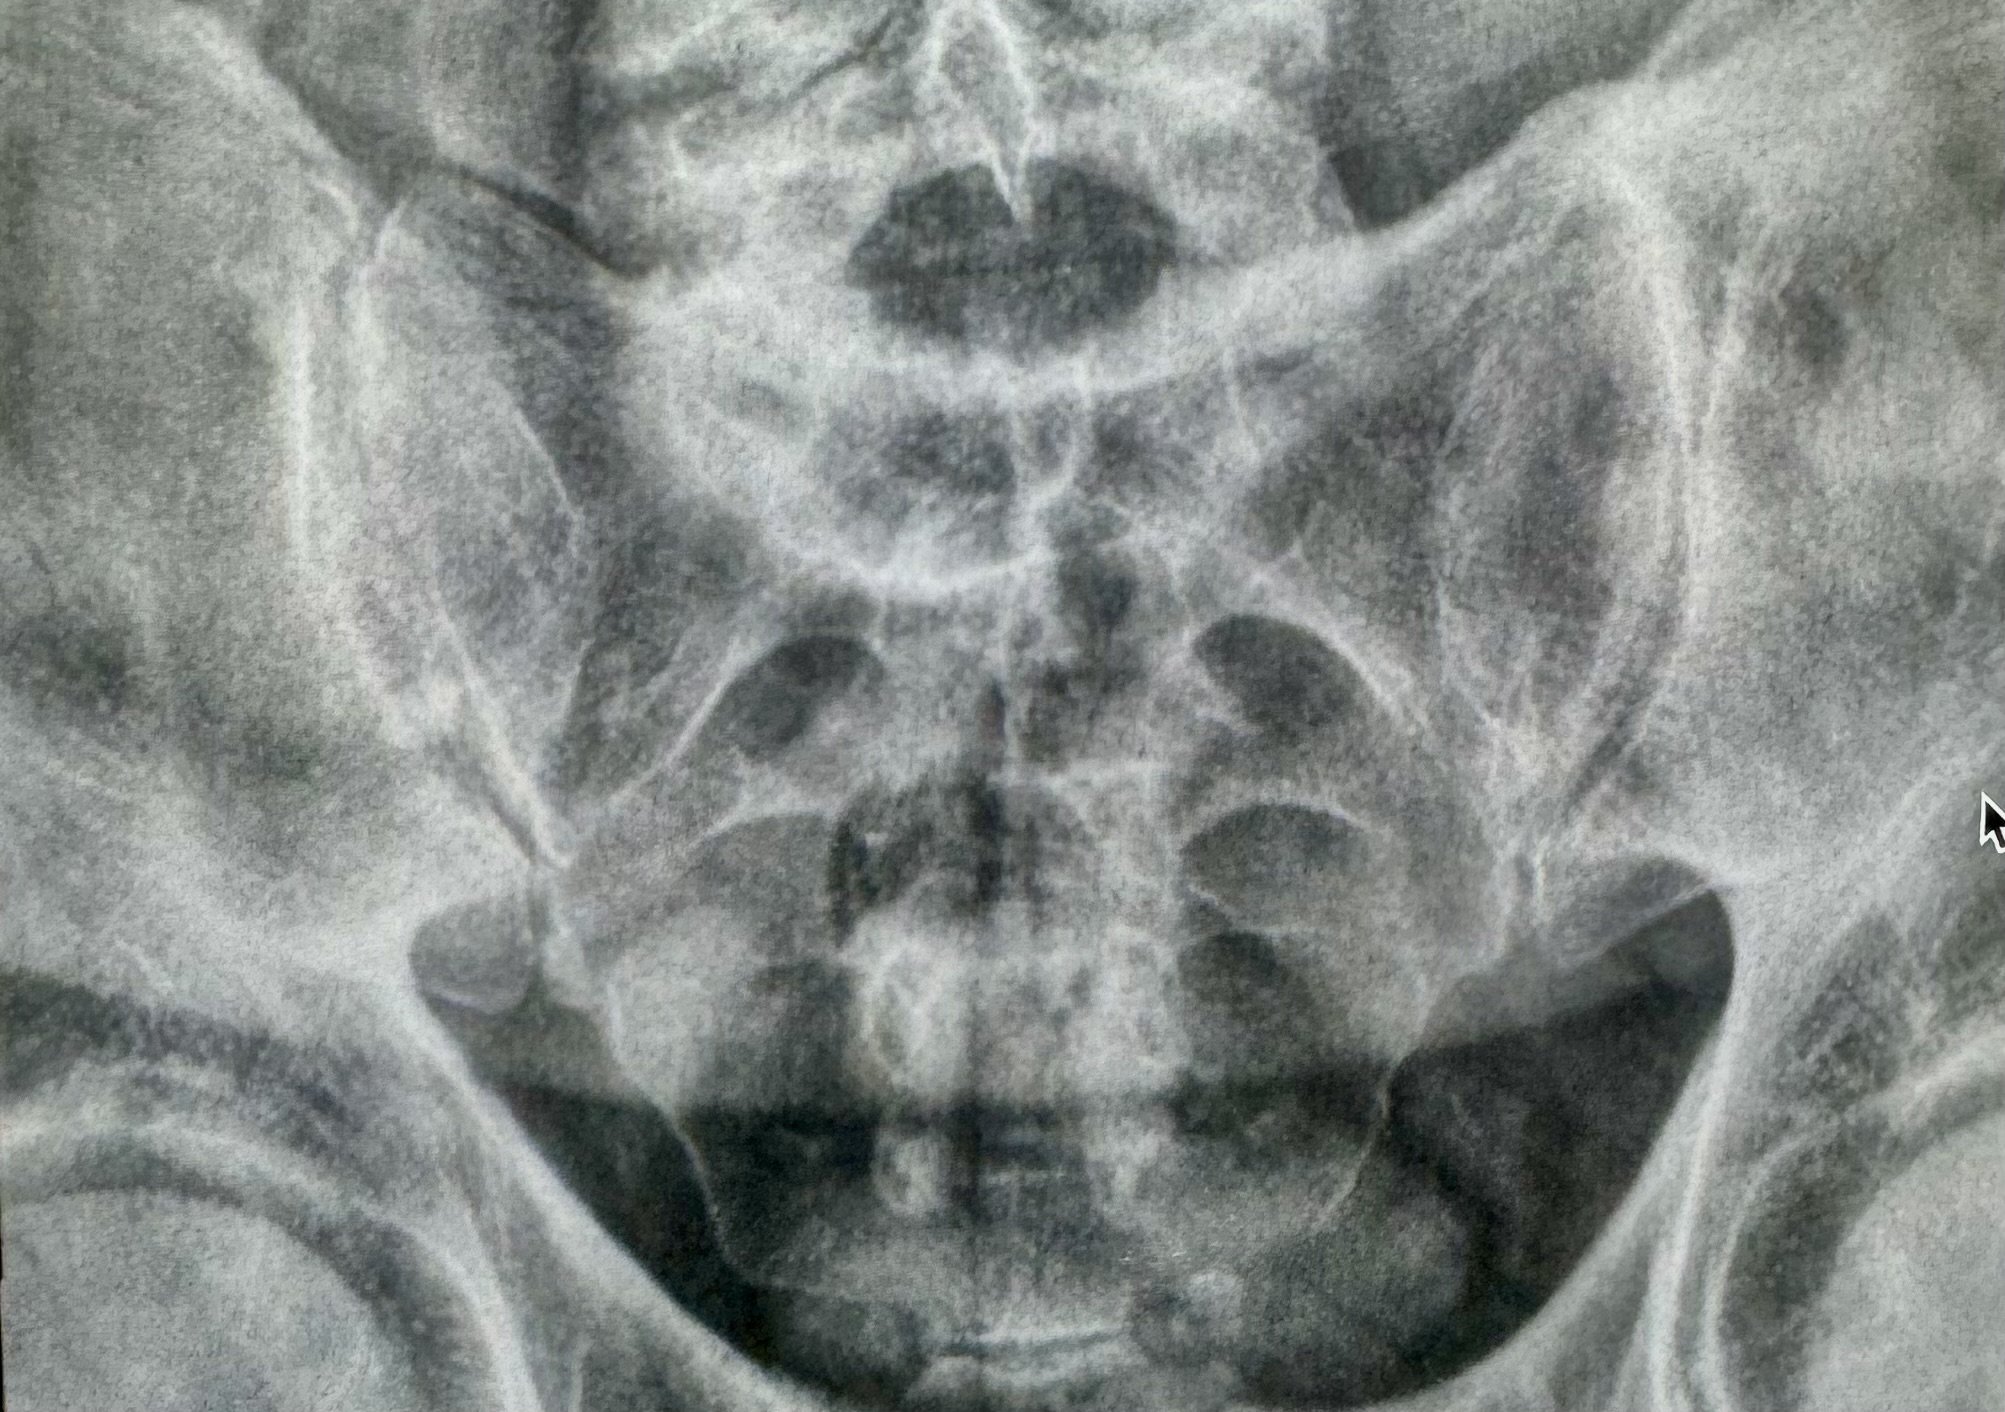

Diagnosing sacroiliitis typically involves a combination of medical history review, physical examination, and imaging studies such as X-rays, MRI, or CT scans to assess the extent of joint inflammation and rule out other potential causes of lower back pain and discomfort.